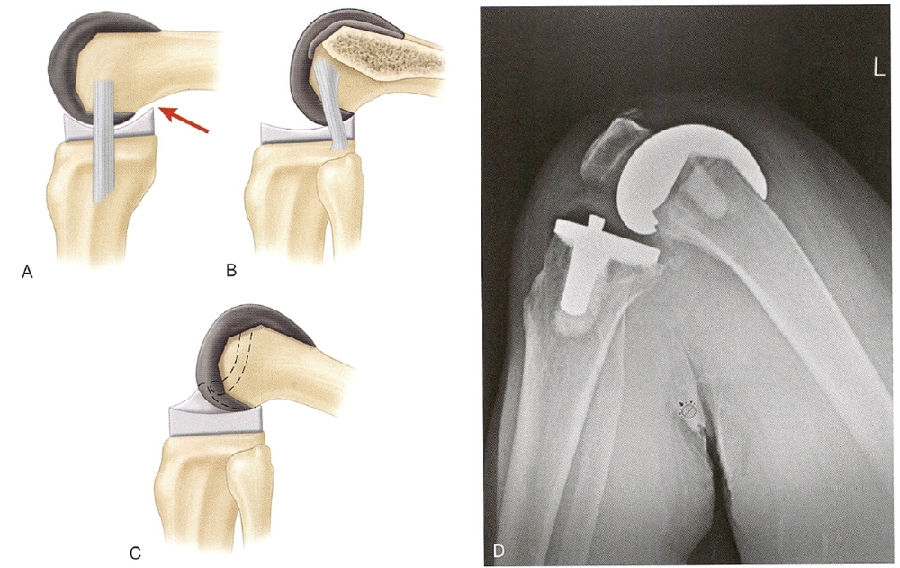

在保留后交叉韧带的情况下,股骨的后滚现象是通过膝关节屈曲过程中由于PCL的张力来完成的(图4)PCL过度紧张会导致术后屈曲角度下降或者过度的股骨后滚,可能会加快聚乙烯的磨损。相反,若PCL在屈曲过程中没有足够的张力,股骨后滚现象就无法实现。为了获得PCL保留型假体的最佳功能和寿命,必须精确地平衡PCL。

图4 A.随着后髁偏距的丧失和股骨假体在胫骨上的前滚,股骨后部和聚乙烯衬垫撞击导致屈曲受限。B.适当的股骨后髁的偏距和功能正常的后交叉韧带(PCL),可以优化屈曲,而不会使股骨后部撞击胫骨衬垫。C.带有立柱和凸轮的后稳定假体可驱动胫骨托上的股骨假体后滚,优化屈曲。D.此X线片为后稳定TKA的一个例子,显示出最佳屈曲后髁得到完全支撑,聚乙烯后唇没有边缘负荷